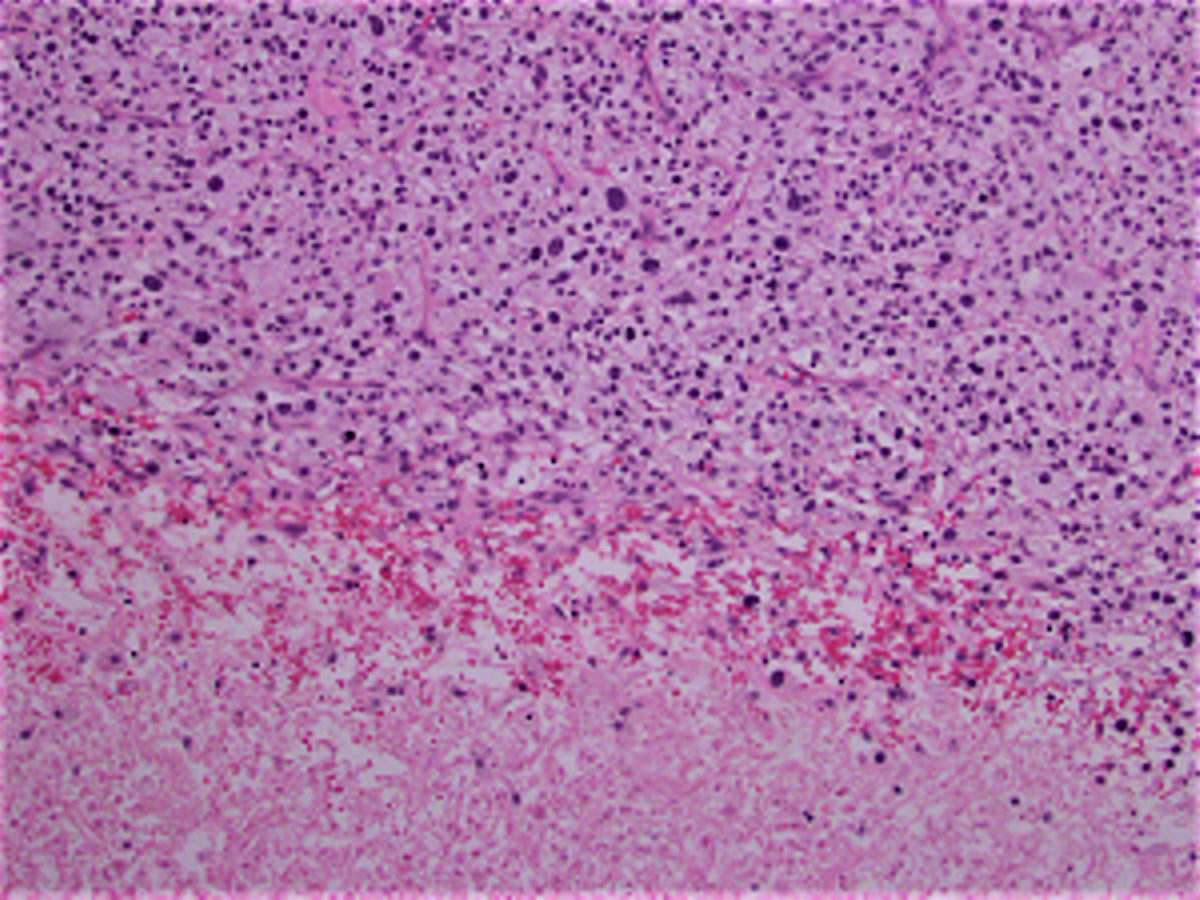

Grossly, the original resection specimen revealed a 17 cm in greatest dimension firm, rubbery lesion with foci of hemorrhage and necrosis. Microscopically, the tumor was mainly composed of sheets of large epithelioid cells with clear cytoplasm and large, pleomorphic nuclei. There were areas of coagulative necrosis. Immunohistochemical stains were performed and the tumor was negative for cytokeratin, S-100, PAX8, RCC, CD10, melan-A, SMA, desmin, caldesmon and HMB-45, while diffusely and strongly positive for vimentin. The tumor recurred again and the patient underwent another chest wall resection which revealed tumor cells which were morphologically similar to the first recurrence with sheets of cells with clear cytoplasm and large, pleomorphic nuclei and foci of necrosis (Figures 1-4).